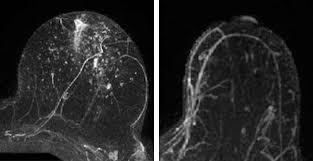

Can A Ct Scan Show Breast Cancer - Cureus Hematoma Mimicking Breast Cancer On Ct Scan And Breast Ultrasound : Doctors can combine pet scans with ct scans.. A pet/ct scan is a newer technology used to create images of the body's cells as they work. However, multidetector computed tomography (ct) often provides the first images of the breast when scanning is performed for pulmonary or cardiac disease. Yes though that is not the test of choice. I went to a breast cancer disucussion given by my local hospital during october. It's an effective imaging test for finding cancer and learning its stage.

However, multidetector computed tomography (ct) often provides the first images of the breast when scanning is performed for pulmonary or cardiac disease. My bone mets were discovered during a bone scan (i.e. It is common for patients to receive a diagnosis for cancer of unknown primary. Breast pet scans are known as positron emission mammography (pem). Ct scan (computerized tomography) of the chest, abdomen, and pelvis;

The term tomography comes from the greek words tomos (a cut, a slice, or a section) and graphein (to write or record). My bone mets were discovered during a bone scan (i.e. This test is most often used to look at the chest and/or belly (abdomen) to see if breast cancer has spread to other organs. Doctors often use ct scans to help them guide a needle to remove a small piece of tissue. Nuclear) and show up on my ct scans as well. When you do a ct scan it is to find the tumors or other suspicious spots in your lungs, adrenal gland, liver, ribs and parts nearby. Bone scans and ct scans are not routine tests for breast cancer and are only done if the cancer has a high risk of spreading. Each picture created during a ct procedure. Pet scans can also help to assess whether metastatic breast cancer is responding to the treatment. Mammography is currently the preferred examination for breast cancer screening; However, your doctor may call this a pet scan. If you have more tests, your risk increases. It is common for patients to receive a diagnosis for cancer of unknown primary.

A chest ct will usually spot breast cancer as an incidental finding. The ct scan might show signs of cancer, but that cancer might not be active for example, it could be scar tissue left over from cancer killed off by your treatment Ct scans can show a tumor's shape, size, and location. This can allow for examination of neighboring organs and structures like lymph nodes to check for any signs of disease. Mammography is currently the preferred examination for breast cancer screening; I was told that a bone scan is often used for diagnosis whereas ct scans can be used for follow up scans. This test is most often used to look at the chest and/or belly (abdomen) to see if breast cancer has spread to other organs. A pelvic ct scan can be used to detect several types of cancer. I went to a breast cancer disucussion given by my local hospital during october. In some cases, physicians use all three imaging techniques. Yes though that is not the test of choice. The combination test can provide a clearer picture of the location, spread, and growth of a tumor than either test by itself. The cancer's stage describes the location of cancer, if it spread and if it's changing the function of your organs.

Abdominal Ct Scan Information Mount Sinai New York from ssl.adam.com 5.7k views reviewed >2 years ago. Ct/pet together in one scan is a more advanced scanning method that is especially helpful in detecting and diagnosing cancer in soft tissues. However, multidetector computed tomography (ct) often provides the first images of the breast when scanning is performed for pulmonary or cardiac disease. Yes though that is not the test of choice. Ct scans are inaccurate for treatment monitoring after cancer treatment, a ct scan is unable to determine whether masses leftover are cancerous: My bone mets are checked using ct scans. The equipment can be set to capture a larger area, as well, during a breast ct scan. Bone scans, positron emission tomography (pet), and computed tomography (ct) all continue to be employed alone or in combination for the detection of breast cancers suspected to have spread.